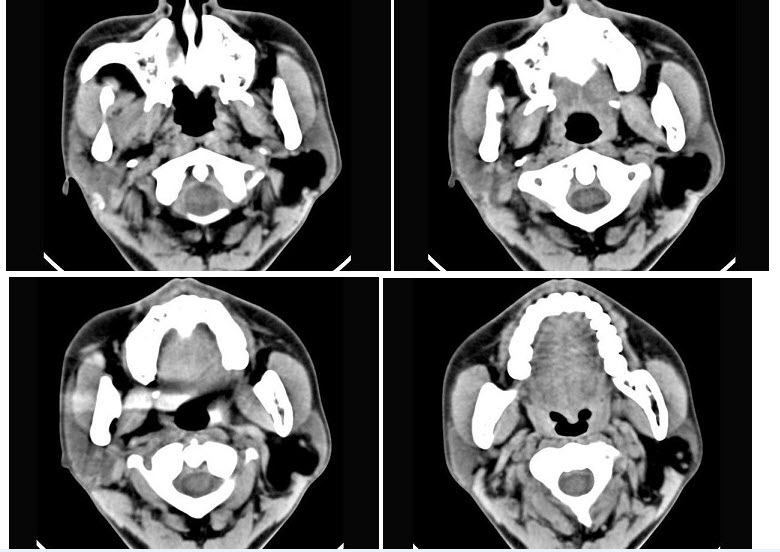

73、多项选择题

男,50岁,声音嘶哑近1年,近来感呼吸困难,CT扫描如图所示,正确的描述或诊断是()

A.喉、气管壁增厚

B.气管后方见软组织肿块

C.肿块内可见致密钙化影

D.喉气管淀粉样变性

E.气管结核